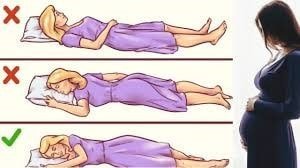

5. آیا در بارداری باید فقط به پهلوی چپ بخوابم؟ آیا می توانم روی شکم هم بخوابم؟

بسیاری از زنان از منابع مختلف می خوانند که باید در تمام دوران بارداری خود به پهلوی چپ بخوابند، اما این مشکل است و ضروری نیست. می توانید به هر دو طرف، راست یا چپ بخوابید.

شما فقط باید از خوابیدن به پشت در اواخر بارداری خودداری کنید. همانطور که شکم شما رشد می کند، خوابیدن به پشت، فشار بیشتری بر رگ های خونی که به رحم شما خون می دهند، وارد می کند. اگر متوجه شدید که در سه ماهه دوم یا سوم بارداری به پشت خوابیده اید، نترسید. فقط به آرامی به سمت چپ یا راست خود بچرخید.

شما می توانید روی شکم خود بخوابید، اما با توجه به رشد رحم و شکم به نقطه ای خواهید رسید که این مدل خوابیدن دیگر برایتان امکان پذیر نیست.